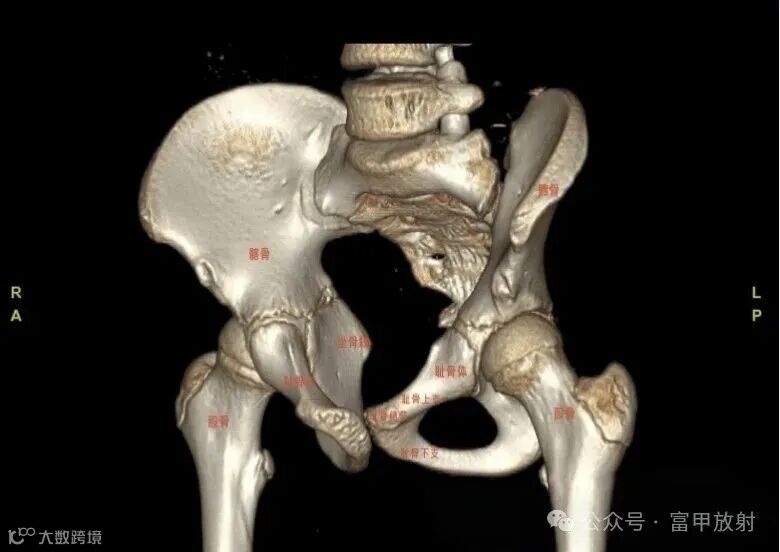

耻骨下支与坐骨分界在哪里?

坐骨结节是坐骨支的突起,是腘绳肌等附着的地方,耻骨结节是耻骨上支内侧缘的突起,腹股沟韧带附着点,在X线上坐骨结节也许估计到,耻骨结节基本上找不到,在这基础上作测量定位置,可靠性会不理想。以下这个简单的方法也许可以帮助到你。